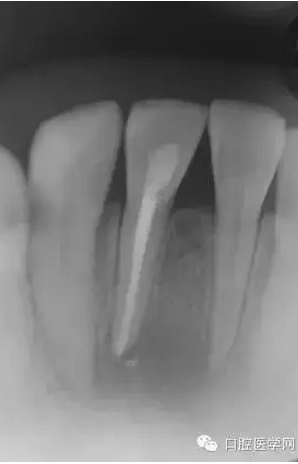

2天后讓患者復(fù)診,查看根管狀態(tài),發(fā)現(xiàn)根管內(nèi)依然有膿液流出,用注射器和針管將根管內(nèi)的膿液吸出來(lái),使用生理鹽水清洗根管后,再用棉球?qū)⒏芊夂谩?天后復(fù)診時(shí),根管狀態(tài)大有好轉(zhuǎn),用NaOCl溶液清洗根管后,為防止根管污染,開(kāi)髓口使用氧化鋅密封。第10天,切口部位基本痊愈,腫脹也完全消失。此后每隔1~2周復(fù)診一次,使用NaOCl溶液清洗根管,根管內(nèi)填充水溶性氫氧化鈣糊劑。從開(kāi)始治療算起,約2個(gè)月后,不再有癥狀,進(jìn)行根管充填。

(圖 3) 根管充填